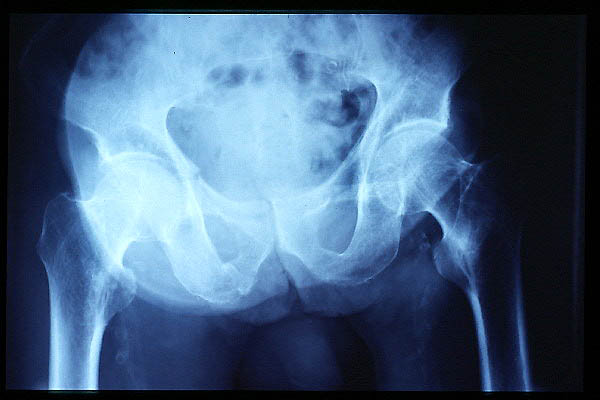

Artrosis avanzada de cadera. Anquilosis.

Artrosis anquilosante de cadera.

Atrosis avanzada de cadera.